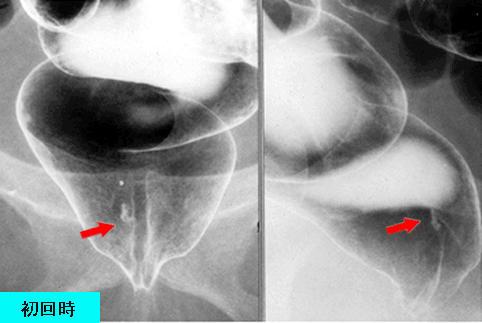

疾患(病理主体)の分類炎症性・潰瘍性疾患/直腸粘膜脱症候群

部位(臓器別)大腸/直腸

検査方法X-P

病変の最大径(ミリ)1〜9